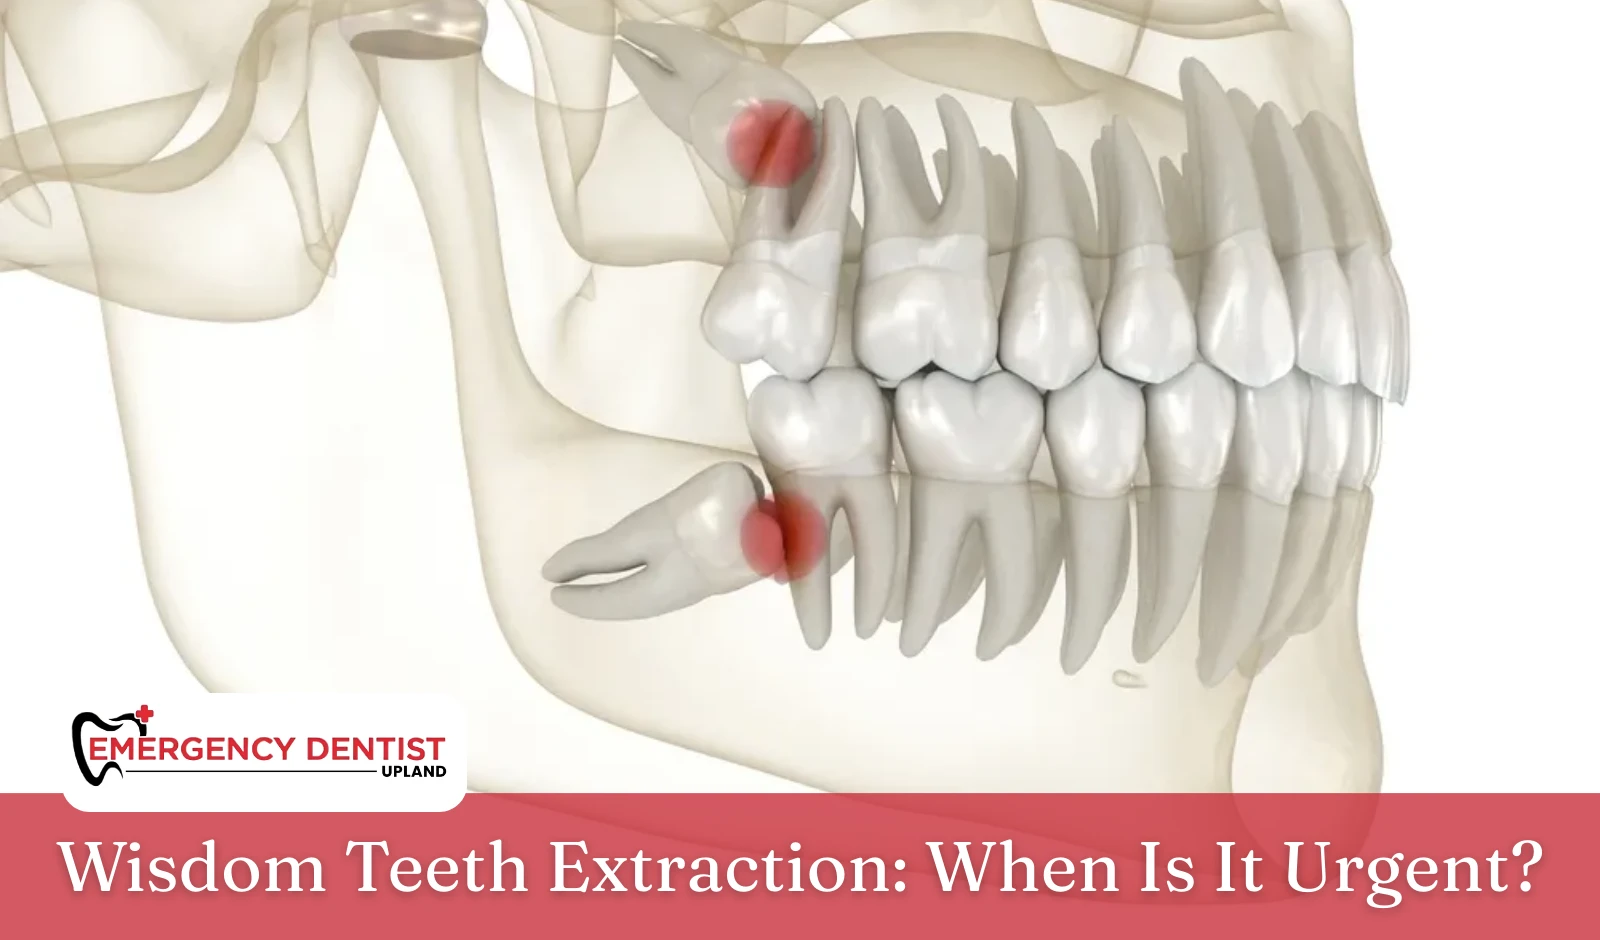

Wisdom teeth are the final molars to develop. They usually appear in the late teenage years or early adulthood. Unfortunately, the jaw often does not have enough room for them to come in properly.

When space is limited, impacted wisdom teeth may become trapped beneath the gum tissue or press against nearby molars. An impacted wisdom tooth may remain partially hidden or grow at an angle, making it difficult to clean.

This increases the risk of:

- Persistent pain and swelling

- Irritated or infected gum tissue

- Gum disease

- Tooth decay

- Development of fluid filled sacs around the tooth

When these concerns begin, a dentist or oral surgeon may recommend wisdom tooth extraction to protect long-term oral health and prevent worsening damage.